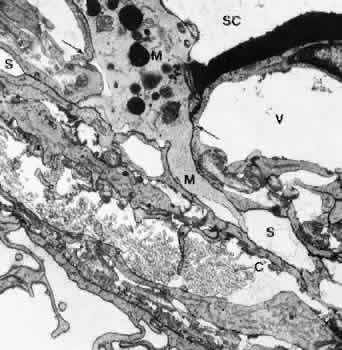

Fig. 15. Electron micrograph of sagittal section of the inner wall of Schlemm's canal (SC) after perfusion with cationized ferritin (CF) (cynomolgus monkey, × 21,000). Note the labeling of cell membranes with cationized ferritin and the enlarged paracellular route (P).E, endothelial cells of the canal; GV, giant vacuole; S, subendothelial cells of cribriform layer; V, small vacuole. (Epstein DL, Rohen JW: Morphology of the trabecular meshwork and inner wallendothelium after cationized ferritin per-fusion in the monkey eye. InvestOphthalmol Vis Sci 32:160, 1991)

If IOP is slightly elevated, only the endothelial cells bulge into the lumen of the canal, thus forming large vacuoles, usually called giant vacuoles. Since Holmberg33 first described these “giant vacuoles” within the inner wall endothelium of Schlemm's canal, the discussion about their functional significance has never been resolved.34 Many of the giant vacuoles communicate with the subendothelial space by way of an often large opening, but very few communicate with the lumen of Schlemm's canal. If there is a communication with the canal, it is usually by a small pore on the canal side of the cell.35 When serial sections are employed, it is possible to demonstrate that some “vacuoles” have openings on the inner and outer sides, thus forming transcellular microchannels. Tripathi34,36 proposed that the endothelial cells lining Schlemm's canal have the ability to transfer aqueous humor in bulk by a cyclical pressure-dependent process that starts initially as an invagination from the trabecular side and proceeds to the formation of a transcellular channel by a perforation in the outer membrane of the vacuole. This hypothesis has, however, not yet been verified. On the other hand, it is now generally accepted that both the frequency and size of giant vacuoles are proportional to the pressure in the anterior chamber at the time of fixation.37 Nearly 20,000 pores have been counted at the luminal side of the inner wall endothelium in human eyes. Therefore, as calculations showed, only 5% to 10% of the entire resistance can be localized within the endothelial lining of human eyes.35,38 This, again, points to the assumption that the subendothelial layers play the major role in forming and possibly regulating outflow resistance. Because occasionally ground substance or particles are found within the giant vacuoles, the transcellular channel system may provide a mechanism by which extracellular material can be “cleared” or “washed out” from he cribriform layer. Inomata and associates39 have shown in cynomolgus monkeys that particles suspended in gelatin solution pass through the transcellular microchannels of the endothelial lining, as do erythrocytes if perfused through the anterior chamber.

The endothelial cells of Schlemm's canal are bound together by maculae adherentes and tight junctions.8,37 However, these tight junctions do not form zonulae occludentes, but in places the adjacent cell membranes are separated, forming meandering pathways between interdigitating cell processes. These pathways are often open toward both the cribriform layer and the lumen of the canal (Fig. 16). Anterior chamber perfusion with cationized ferritin in rhesus monkeys has shown that these particles predominantly pass through the paracellular routes.8,9 Often these routes are locally expanded, so that in sagittal sections “vacuole-like” structures are formed.9 According to our observations, macrophages and leukocytes mostly pass through the paracellular routes to leave the eye rather than through the transcellular channels (Fig. 17).

Fig. 16. Structure of the inner wall endothelium (E) of Schlemm's canal (SC) showing a transcellular pathway through a giant vacuole (GV) and a paracellular route (arrow) labeled with cationized ferritin (CF). S, subendothelial cells. (Epstein DL, Rohen JW: Morphology of the trabecular meshwork and inner wall endothelium after cationized ferritin perfusion in the monkey eye. Invest Ophthalmol Vis Sci 32:160, 1991)

Fig. 17. Electron micrograph of a sagittal section through the inner wall of Schlemm's canal (SC) after anterior chamber perfusion with cationized ferritin (cynomolgus monkey, × 21,800). Note the large macrophage (M) squeezing through the intercellular space (arrows) of the inner wall endothelium of Schlemm's canal (SC). C, collagenous fibers; V, giant vacuole; S, subendothelial space.